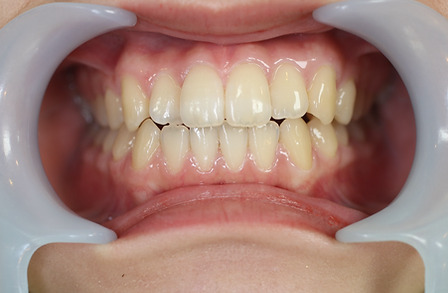

1矯正・マウスピース【治療例1】

治療前

治療後